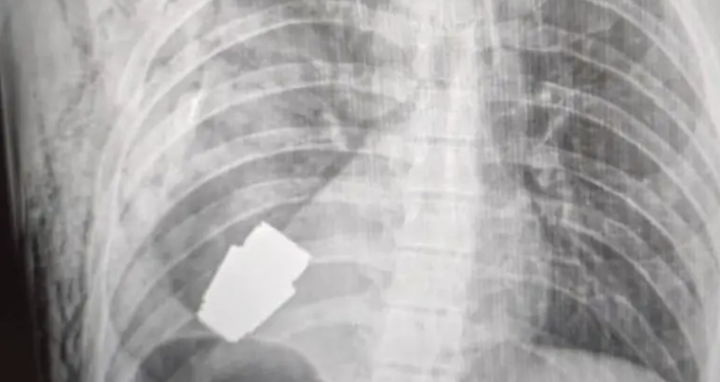

Images shared by the Ukrainian armed forces’ medical service showed an X-ray of the soldier’s chest with the grenade clearly visible inside.

In 2023, a Ukrainian soldier survived after a grenade became lodged in his chestFacebook/Ukraine Medical Force Command

Another image showed a surgeon carefully holding the grenade after successfully removing it from the soldier’s chest, where it had been lodged dangerously close to his heart.